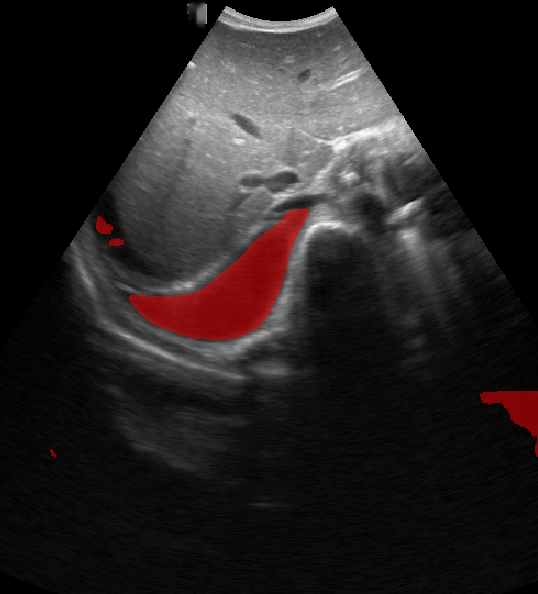

A total of 143 images were acquired from 59 patients. The images were obtained at the left and right PLAPS (PosteroLateral Alveolar and/or Pleural Syndrome) and subcostal views [4] with linear array and curved array (abdominal) ultrasound probes. The data were split according to the use of these probes into two datasets of 51 and 92 images, respectively for linear array and curved array. We denote these datasets as Dataset A (linear array) and Dataset B (curved array). All images were annotated at the time of acquisition to measure the extent of the effusion. These annotations consisted of small crosses at the top and bottom of the deepest area of effusion. See Figure 1 (left column) for example images.

Before being used for training and evaluating the models, each image was automatically cropped using a rectangular/cone mask to remove non-imaging content. Next, we applied an inpainting text algorithm using keras-ocr followed by template matching and edge detection algorithms from opencv to remove the annotations that were added to the images to measure the effusion. Examples of the outputs of this preprocessing are shown in Figure 1 (centre column).

All images in both datasets were manually segmented using the ITK-SNAP software [14] (www.itksnap.org) by a trained observer. Examples of ground truth segmentations are shown in Figure 1 (right column). These segmentations acted as ground truths for training and evaluating the proposed models. Additionally, a second trained observer performed independent segmentations of subsets of 10 random images each from the two datasets. These were used to compute an estimate of inter-observer variability in the manual segmentation process.

Qualitative prediction results of the two proposed models (baseline nnU-Net and nnU-Net with coordinate convolutions) on the two datasets are shown in Figure 2. Tables 1 and 2 summarise the quantitative performances in terms of DSC and area statistics. Histograms of the DSC values are shown in Figure 3. The median DSCs between the manual segmentations on the subsets of 10 images (i.e. the estimates of inter-observer variability) are also shown in Table 1.

It can be seen that, despite having fewer images, the baseline model for Dataset A obtained a higher median DSC than the model for Dataset B. For Dataset A the coordinate convolution model improved the DSC and reduced the area error and bias. In two-tailed Wilcoxon signed rank tests (0.05 significance) the difference between the baseline DSC and that of the coordinate convolution model was found to be statistically significant for Dataset A () but there was no statistically significant difference for Dataset B (). Interestingly, for both Dataset A and Dataset B, both the baseline and coordinate convolution models performed better than the estimate of inter-observer variability. However, we note that the inter-observer variability is quite high (i.e. median DSCs of 0.78 and 0.71), likely reflecting the difficulty and partly subjective nature of the effusion segmentation task. Therefore, it seems likely that the deep learning models are learning to segment effusion in the style of the main observer, which may not always be consistent with the second observer. In addition, the histograms shown in Figure 3 suggest that there are a significant number of failure cases in the outputs of both models (although fewer for the coordinate convolution model for Dataset A), again reflecting the difficulty of the task.

Rows 1-2: Dataset A. Rows 3-4: Dataset B.